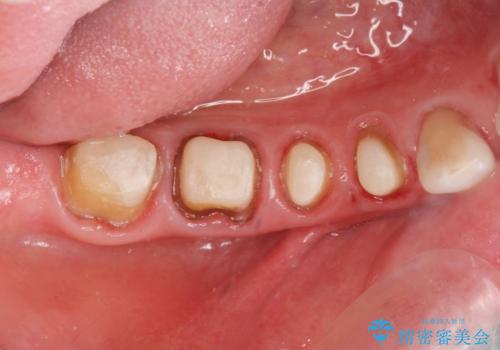

大臼歯 再根管治療

- 銀歯を白くしたいとの希望で来院されました。

せっかく銀歯を白くしても後々根管治療が必要になり、また壊して再治療を行うことを避けたいとの事でしたので、再根管治療から行っていきます。

ただ銀歯を白くするのではなく長期的な予後には歯の内部、根管治療の成功が必要不可欠です。